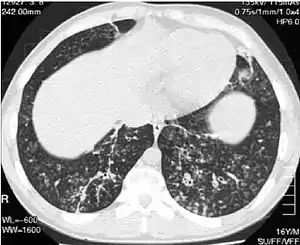

| High-resolution computed tomography images of the lower chest in a 16-year-old boy with diffuse panbronchiolitis | |

The diagnosis of DPB requires analysis of the lungs and bronchiolar tissues, which can require a lung biopsy, or the more preferred high resolution computed tomography (HRCT) scan of the lungs.[7] The diagnostic criteria include severe inflammation in all layers of the respiratory bronchioles and lung tissue lesions that appear as nodules within the terminal and respiratory bronchioles in both lungs.[4] The nodules in DPB appear as opaque lumps when viewed on X-rays of the lung, and can cause airway obstruction, which is evaluated by a pulmonary function test, or PFT.[6] Lung X-rays can also reveal dilation of the bronchiolar passages, another sign of DBP. HRCT scans often show blockages of some bronchiolar passages with mucus, which is referred to as the "tree-in-bud" pattern.[7] Hypoxemia, another sign of breathing difficulty, is revealed by measuring the oxygen and carbon dioxide content of the blood, using a blood test called arterial blood gas. Other findings observed with DPB include the proliferation of lymphocytes (white blood cells that fight infection), neutrophils, and foamy histiocytes (tissue macrophages) in the lung lining. Bacteria such as H. influenzae and P. aeruginosa are also detectable, with the latter becoming more prominent as the disease progresses.[4][5] The white blood, bacterial and other cellular content of the blood can be measured by taking a complete blood count (CBC). Elevated levels of IgG and IgA (classes of immunoglobulins) may be seen, as well as the presence of rheumatoid factor (an indicator of autoimmunity). Hemagglutination, a clumping of red blood cells in response to the presence of antibodies in the blood, may also occur. Neutrophils, beta-defensins, leukotrienes, and chemokines can also be detected in bronchoalveolar lavage fluid injected then removed from the bronchiolar airways of individuals with DPB, for evaluation.[4][9]